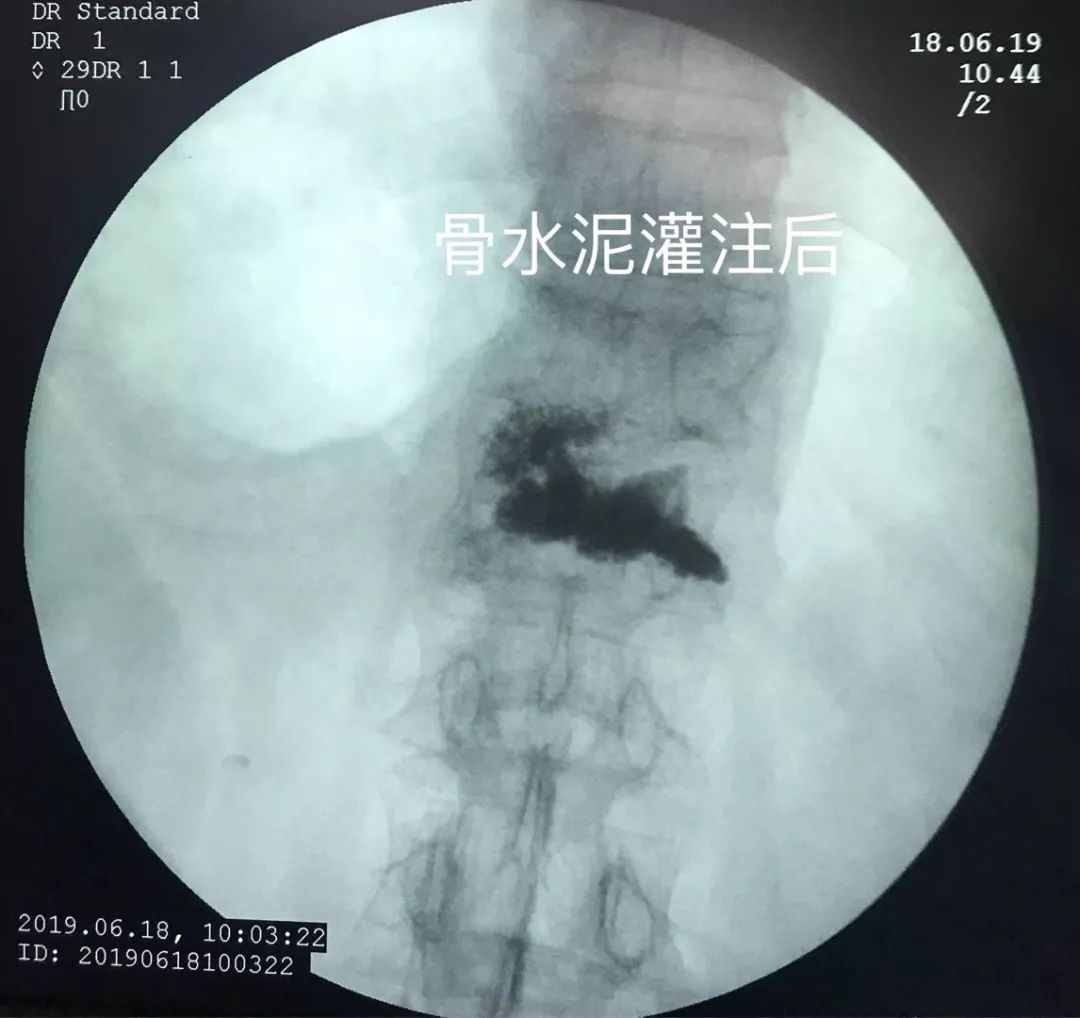

骨水泥灌注术后

灌注骨水泥既可以起到椎体成型的作用,还可以起到止痛的作用。如果是椎体肿瘤,还可以对肿瘤细胞起到杀灭的作用。